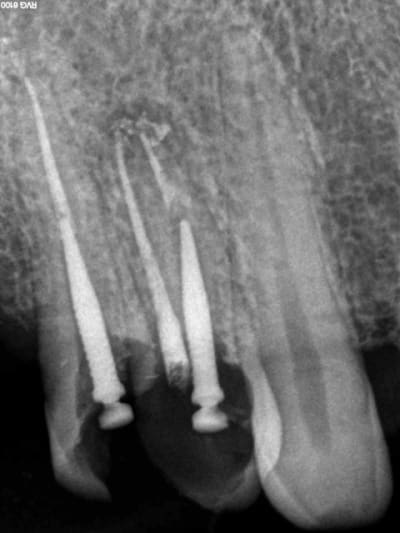

Aujourd'hui patient en urgence ca tombe bien pour une fois synchro avec un lapin.

45 mn de turbinage intensif 2 endos + 2 SC 33; On cote comment les radios ?

Z6, SC 20, Z3,Z3, SC20, Z3, Z3, SC 33, Z3, SC 33, Z3 ?

Tssss, Z6 radio de diagnostic, endo Z3 + Z3 par endo, SC33 radios de controle Z3, 1 par acte.

Avant c'était Z6 par séance quel que soit le nombre de clichés. Je n'ai pas fait les 2 endos en meme temps simplement la première à été faite en mode turbo, j'avais donc du temps en rab et j'ai fait la seconde après. A la limite un Z 3 de trop sur les SC 33.